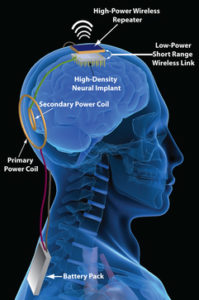

தற்போது, ஆழ் மூளை தூண்டுதல் (Deep Brain Stimulation) எனும் சிகிச்சை முறையில், உடலில் ஒரு கருவி வைக்கப்பட்டு, குறிப்பான இடங்களில் பொருத்தப்படும் அதன் மின்வாய்களின் மூலம் மின் தூண்டுதல்களை செலுத்தி நரம்பு மண்டலத்தை சிதைக்கும் நடுக்குவாத (Parkinson’s) நோய்க்கு மருத்துவம் அளிக்கப்படுகிறது.

கருப்பு ஆடி (Black Mirror) எனும் தொலைக்காட்சி தொடர்களில் காட்டப்படும் நினைவுப் பதிய கருவிகள் தற்போது நடைமுறையில் உள்ள DBS அமைப்பு முறையினாலெயே கூடுமானவரையில் உருவாக்கப்பட்டிருக்கும். இத்தகைய அமைப்பு முறைகளில் உள்ள பாதுகாப்புக் குறைபாடுகள் குறித்து காஸ்பெர்ஸ்கி ஆய்வகமும் (Kaspersky Labs) ஆக்ஸ்போர்ட பல்கலைக்கழகமும் இணைந்து ஆய்வு மேற்கொண்டன. அவர்களது ஆய்வு முடிவுகள் மிகவும் சிறப்பாக வெளிவந்துள்ளன.

ஏற்கெனவே இருக்கும் பதியங்களில், பாதுகாப்பு அம்சங்கள் மிகவும் வலுவற்ற நிலையில் இருப்பதாகத் தெரிவிக்கின்றனர் ஆய்வாளர்கள். மருத்துவர்கள் மற்றும் அறுவைச் சிகிச்சை நிபுணர்கள் பயன்படுத்தும் மருத்துவ மேலாண்மைக் கருவிகளுடன் தகவல் பரிமாற்றத்துக்காக இணைகையில் இத்தகைய பாதுகாப்பு அபாயங்கள் இருக்கின்றன. இத்தகைய கருவிகளில் தற்போது நடைமுறையில் உள்ள அதிநவீன கருவிகள் கூட புளூடூத் தொழில்நுட்பத்திலேயே தகவல்களை பரிமாறிக் கொள்கின்றன. இந்த புளூடூத் தொழில்நுட்பம், புகழ் பெற்றதாகவும், எளிமையானதாகவும் இருப்பினும் இது பாதுகாப்புக் குறைபாடு கொண்டதாகவே இருக்கிறது

அத்தகைய கருவிகளுக்கு இயல்பாகவே ஒரு பின்வாசல் வழி ஒன்று தேவைப்படுகிறது. நெருக்கடி நேரத்தில் மருத்துவ நிபுணர்கள் அதன் வழியாக அக்கருவியை அணுக முடியும். அதே நேரத்தில் இதில் உள்ள சிக்கலையும் ஆராய்ச்சிக் குழு அடிக்கோடிட்டுக் காட்டுகிறது. விஐபி நோயாளி ஒருவரின் கருவியை அணுகும் வழியை ஒருவருக்கு மருத்துவ நிபுணர்கள் விற்பதை எதுவும் தடுக்கப் போவது இல்லை. அதே போல, தயாரிப்பின் போது அமைக்கப்பட்ட கடவுச்சொல்லை (factory-preset password) மாற்றுவதற்கு மறந்து போவதை தடுக்கப் போவது இல்லை.